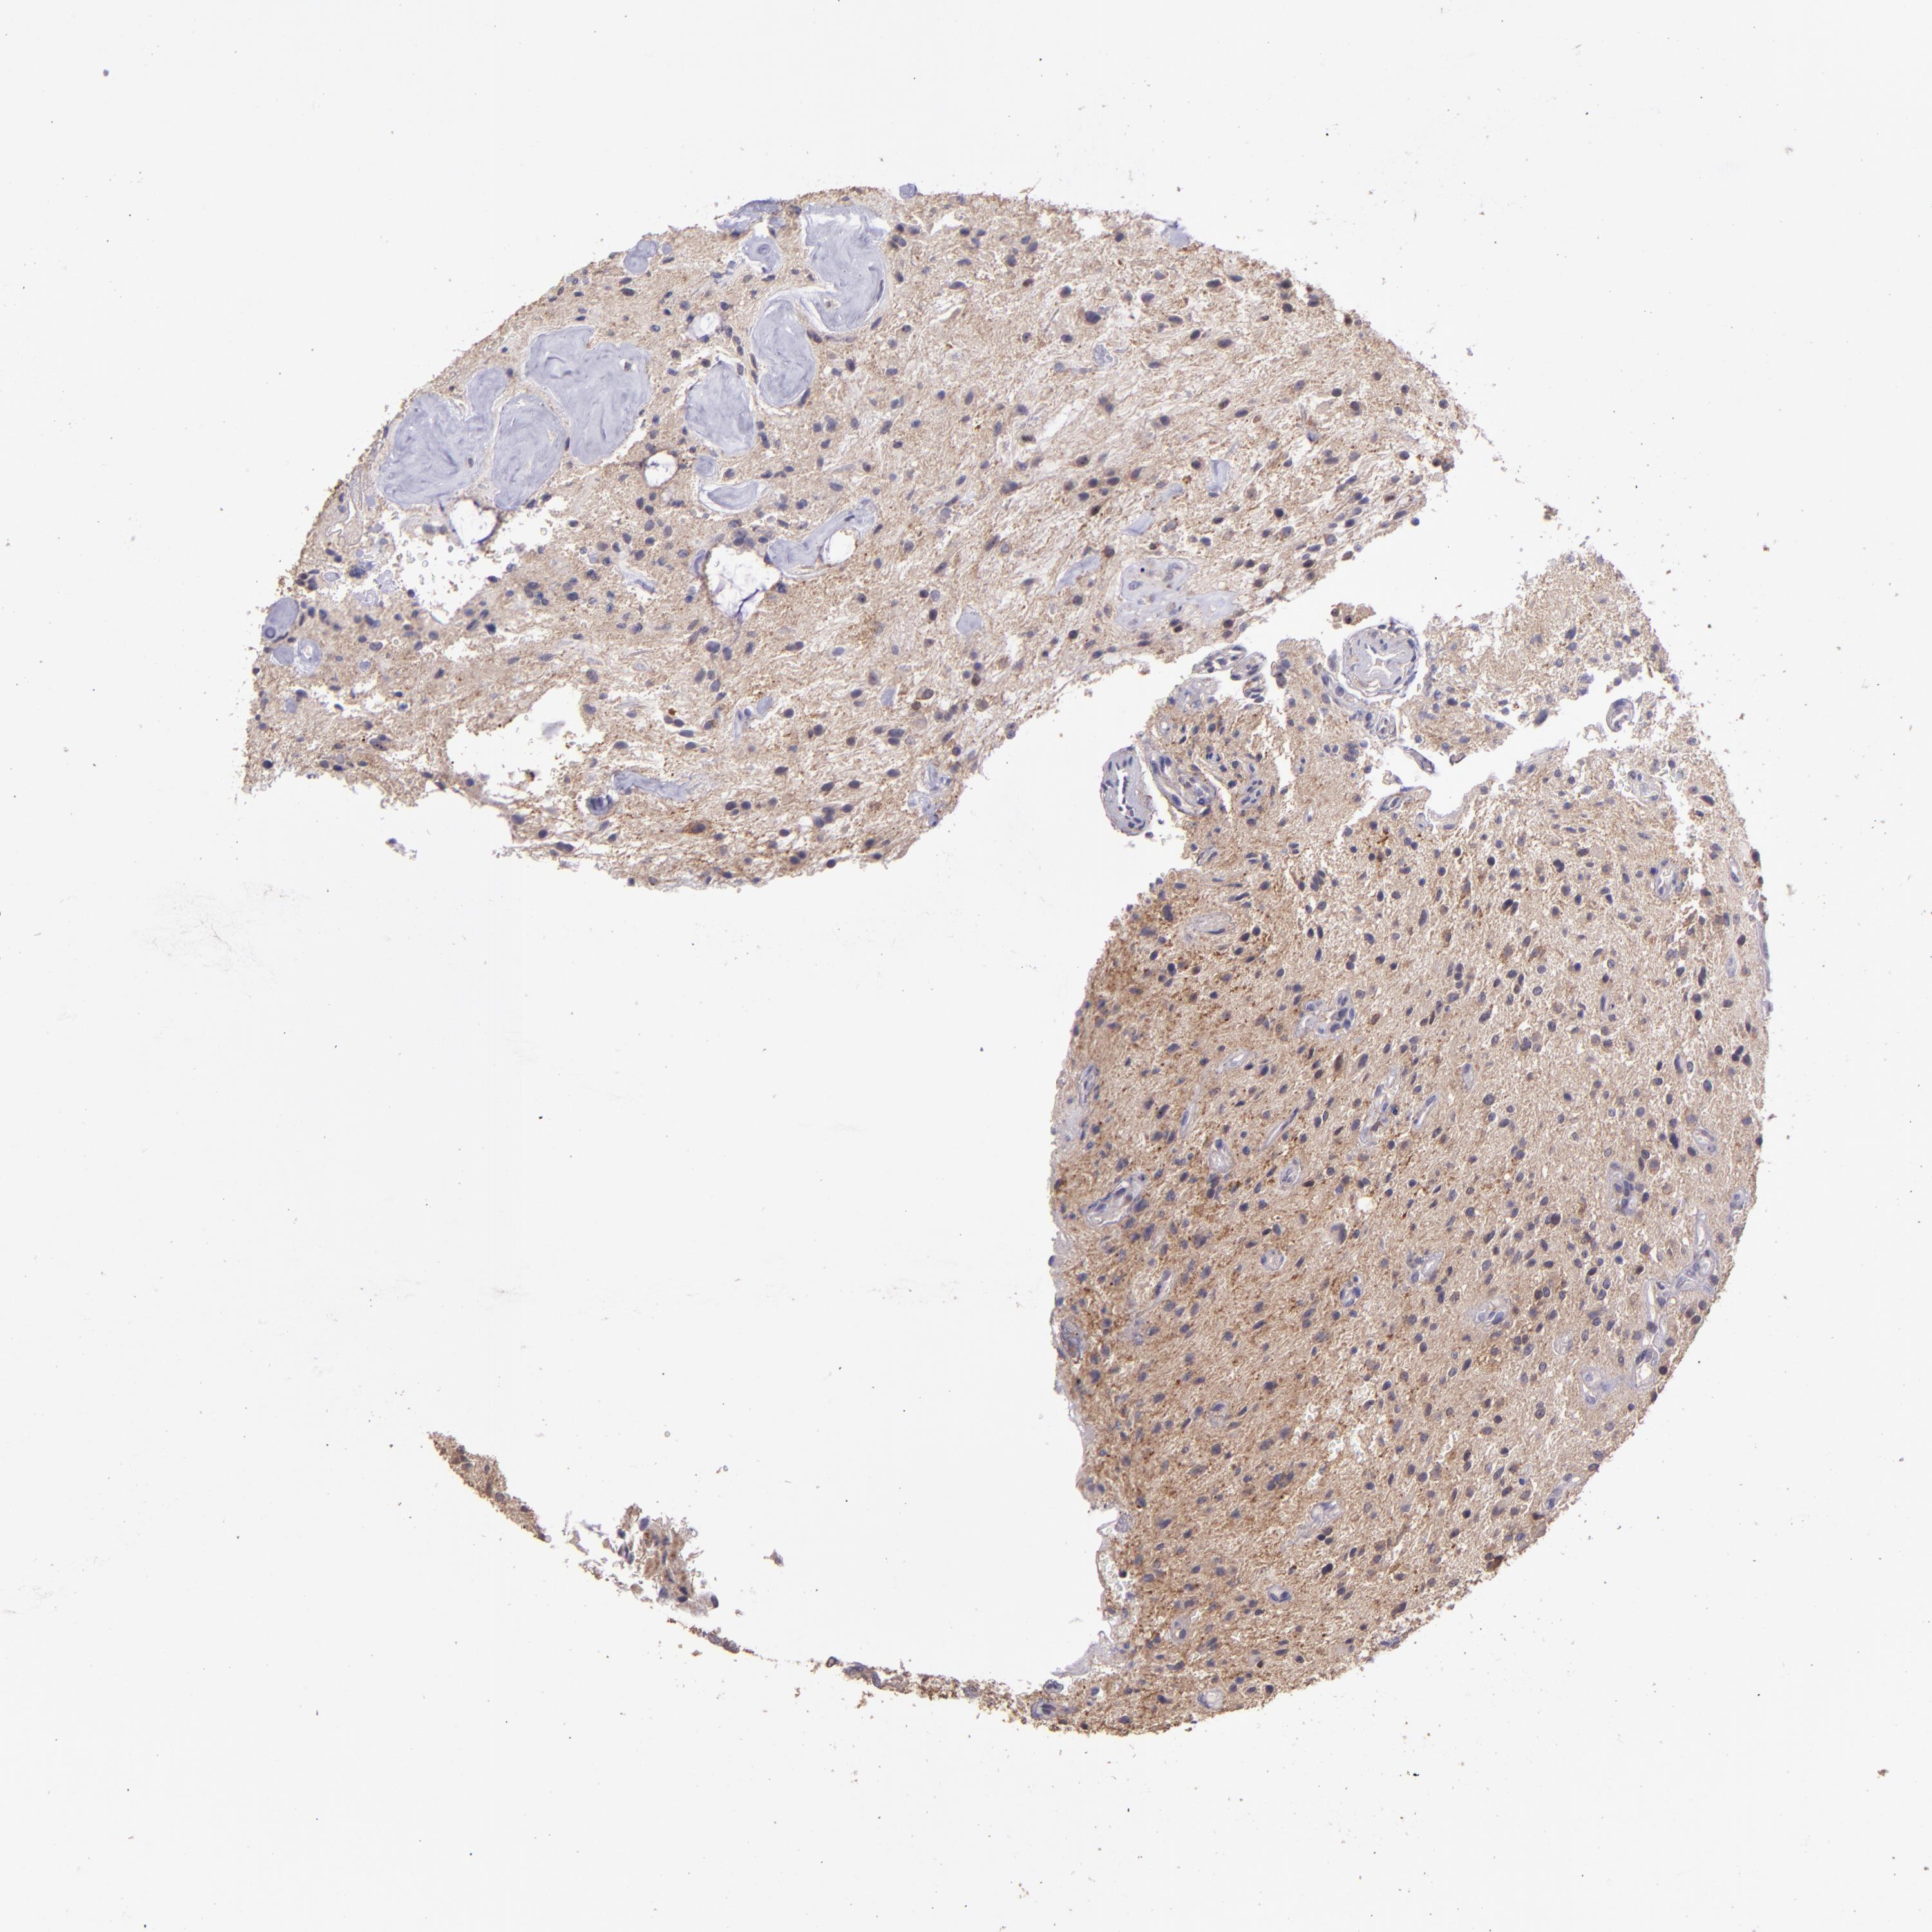

GLIOMA - Protein expressioni

A mouse-over function shows sample information and annotation data. Click on an image to view it in a full screen mode. Samples can be filtered based on level of antibody staining by selecting one or several of the following categories: high, medium, low and not detected. The assay and annotation is described here.

Note that samples used for immunohistochemistry by the Human Protein Atlas do not correspond to samples in the TCGA dataset.

Antibody stainingi

Antibody staining in the annotated cell types in the current human tissue is reported as not detected, low, medium, or high, based on conventional immunohistochemistry profiling in selected tissues. This score is based on the combination of the staining intensity and fraction of stained cells.

Each image is clickable and will lead to virtual microscopy that enables deeper exploration of all samples and also displays staining intensity scores, fraction scores and subcellular localization as well as patient and tissue information for each sample.

Antibody HPA001667

Antibody CAB016724

Staining

High

Medium

Low

Not detected

Intensity

Strong

Moderate

Weak

Negative

Quantity

>75%

75%-25%

<25%

None

Location

Nuclear

Cytoplasmic/membranous

Cytoplasmic/membranous,nuclear

Glioma, malignant, High grade

Glioma, malignant, Low grade

Glioma, malignant, NOS